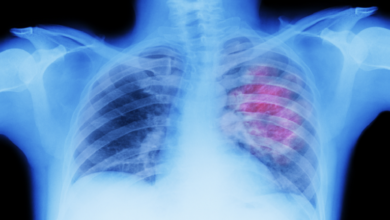

كشفت وزارة الصحة والحماية الاجتماعية، اليوم الجمعة 31 دجنبر الجاري، رصد 2034 حالة إصابة مؤكدة بفيروس كورونا، ليرتفع اجمالي عدد حالات الإصابة خلال الـ24 ساعة الماضية بالمملكة إلى 963 حالة.

بالمقال، تيقنت الوزارة ضمن نشرتها الخاصة بتتبع ورصد الوبائي من تسجيل 660 حالة شفاء من المرض، ليصل مجموع حالات الشفاء التامة من المرض إلى 940193 حالة شفاء، فيما تم تسجيل 5 وفيات، ليرتفع عدد الوفيات إلى 14849 حالة وفاة.

وتبعًا للمصدر ذاته، فقد بلغ عدد الأشخاص الذين تلقوا الجرعة الأولى من اللقاح المضاد لكورونا 24557876 شخصا، فيما بلغ عدد الملقحين بالجرعة الثانية 22931922شخصا، وبالنسبة لعدد الملقحين بالجرعة الثالثة، فقد وصل إلى 2991107 شخصا.